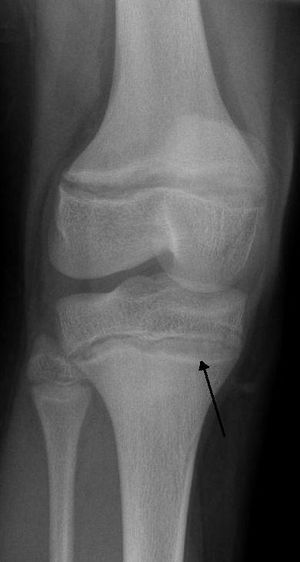

An X ray demonstrating the characteristic finding of lead poisoning, dense metaphyseal lines. | |